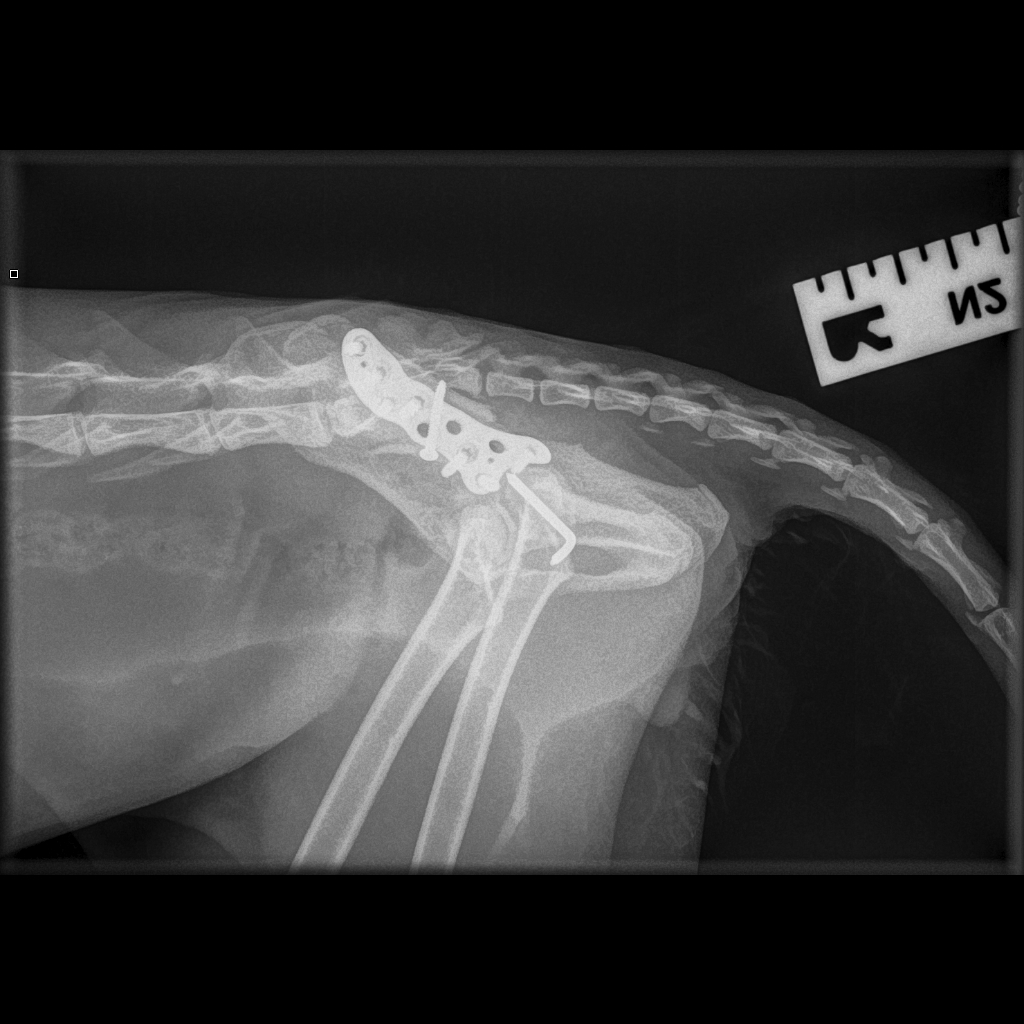

The Lateral Epicondylar Anatomical Plate was developed by Movement’s very own Ben Walton, in collaboration with engineers at Fusion Implants. This locking plate system is designed for the complex anatomy of the lateral epicondyle in breeds of dog such as Springer Spaniels and French Bulldogs.

The plate was designed from CT images from previous patients so that the pre-contouring is a good fit and the screw holes and direction are in the ideal position.

The plate is used in combination with a transcondylar implant such a cortical screw or HIRS implant.